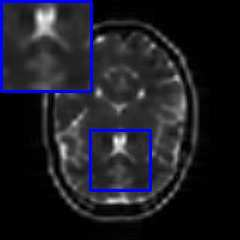

Limited by imaging systems, the reconstruction of Magnetic Resonance Imaging (MRI) images from partial measurement is essential to medical imaging research. Benefiting from the diverse and complementary information of multi-contrast MR images in different imaging modalities, multi-contrast Super-Resolution (SR) reconstruction is promising to yield SR images with higher quality. In the medical scenario, to fully visualize the lesion, radiologists are accustomed to zooming the MR images at arbitrary scales rather than using a fixed scale, as used by most MRI SR methods. In addition, existing multi-contrast MRI SR methods often require a fixed resolution for the reference image, which makes acquiring reference images difficult and imposes limitations on arbitrary scale SR tasks. To address these issues, we proposed an implicit neural representations based dual-arbitrary multi-contrast MRI super-resolution method, called Dual-ArbNet. First, we decouple the resolution of the target and reference images by a feature encoder, enabling the network to input target and reference images at arbitrary scales. Then, an implicit fusion decoder fuses the multi-contrast features and uses an Implicit Decoding Function~(IDF) to obtain the final MRI SR results. Furthermore, we introduce a curriculum learning strategy to train our network, which improves the generalization and performance of our Dual-ArbNet. Extensive experiments in two public MRI datasets demonstrate that our method outperforms state-of-the-art approaches under different scale factors and has great potential in clinical practice.